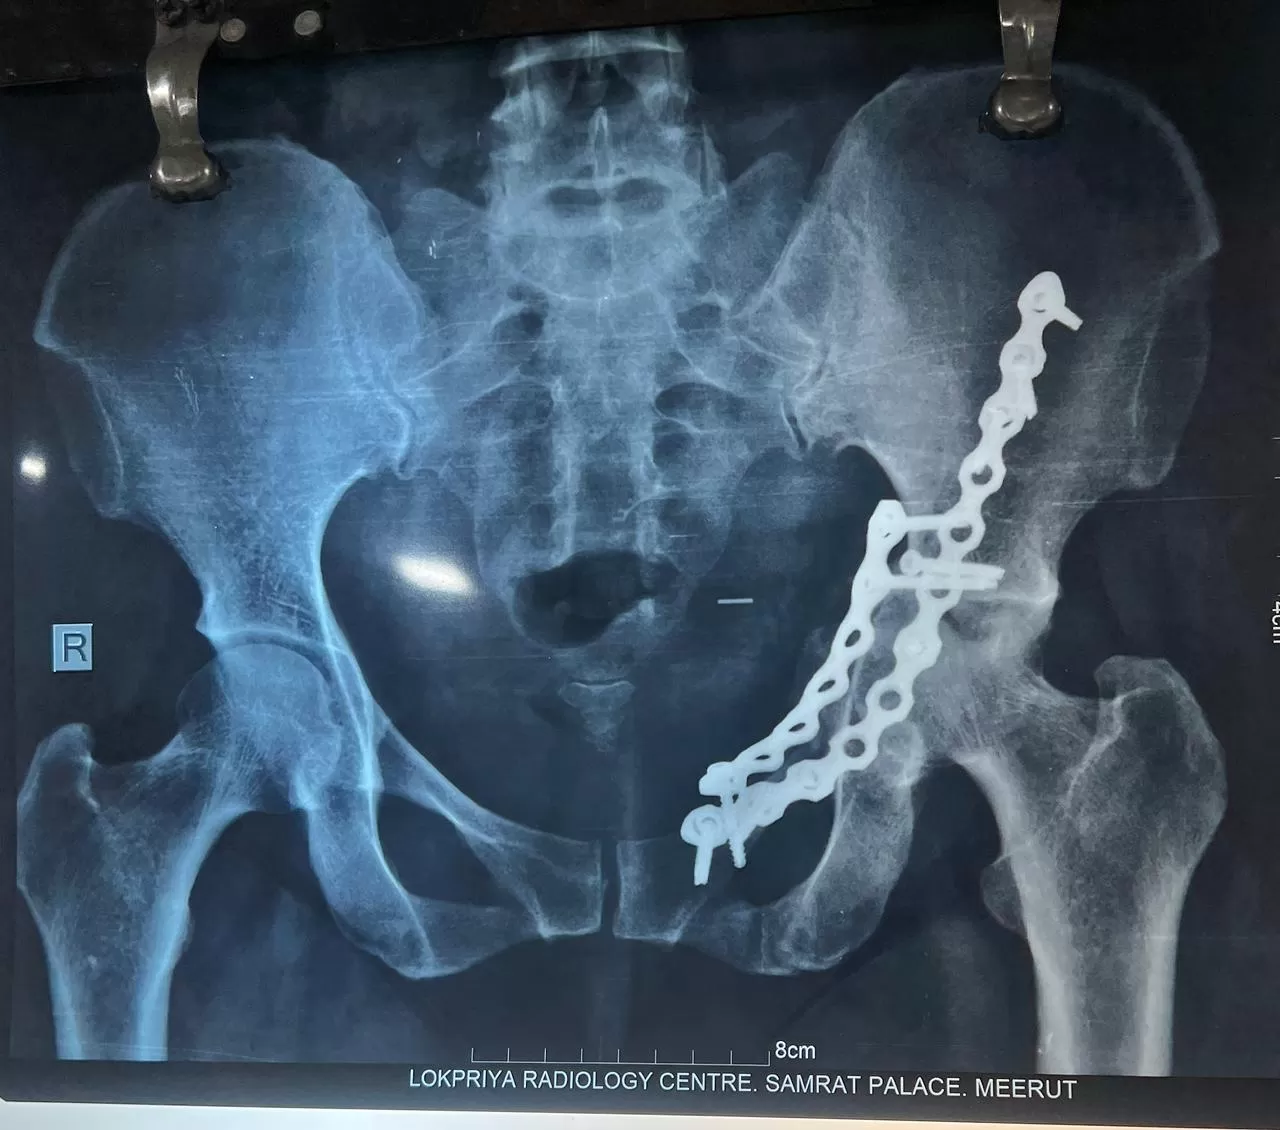

Hemlata

Name: Hemlata

Date of Operation: 7 November 2025

Age: 40 Years

Complex Trauma